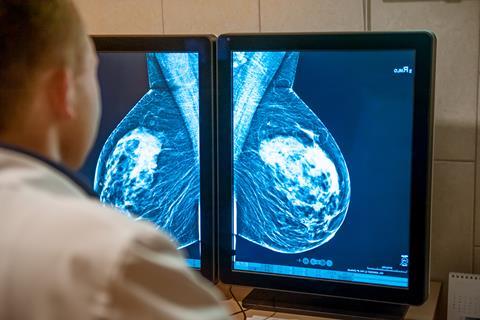

Oestrogen receptor-positive (ER+) breast cancer is typically treated using anti-hormonal therapies designed to deactivate or degrade the oestrogen receptor. This receptor drives abnormal cell proliferation when overactive, making it a crucial target in slowing tumour growth. While many patients respond well to hormone therapy, a proportion develop metastases that eventually stop responding to these treatments.